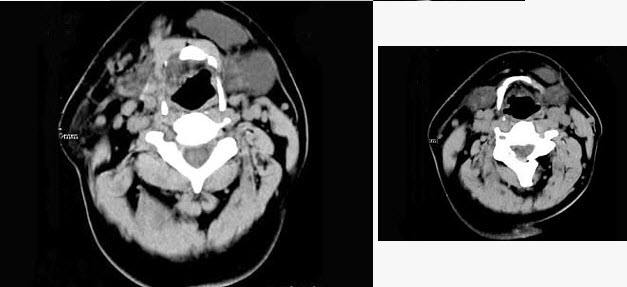

扁桃體惡性腫瘤圖片

扁桃體癌圖 (9)

扁桃體癌圖 (63)